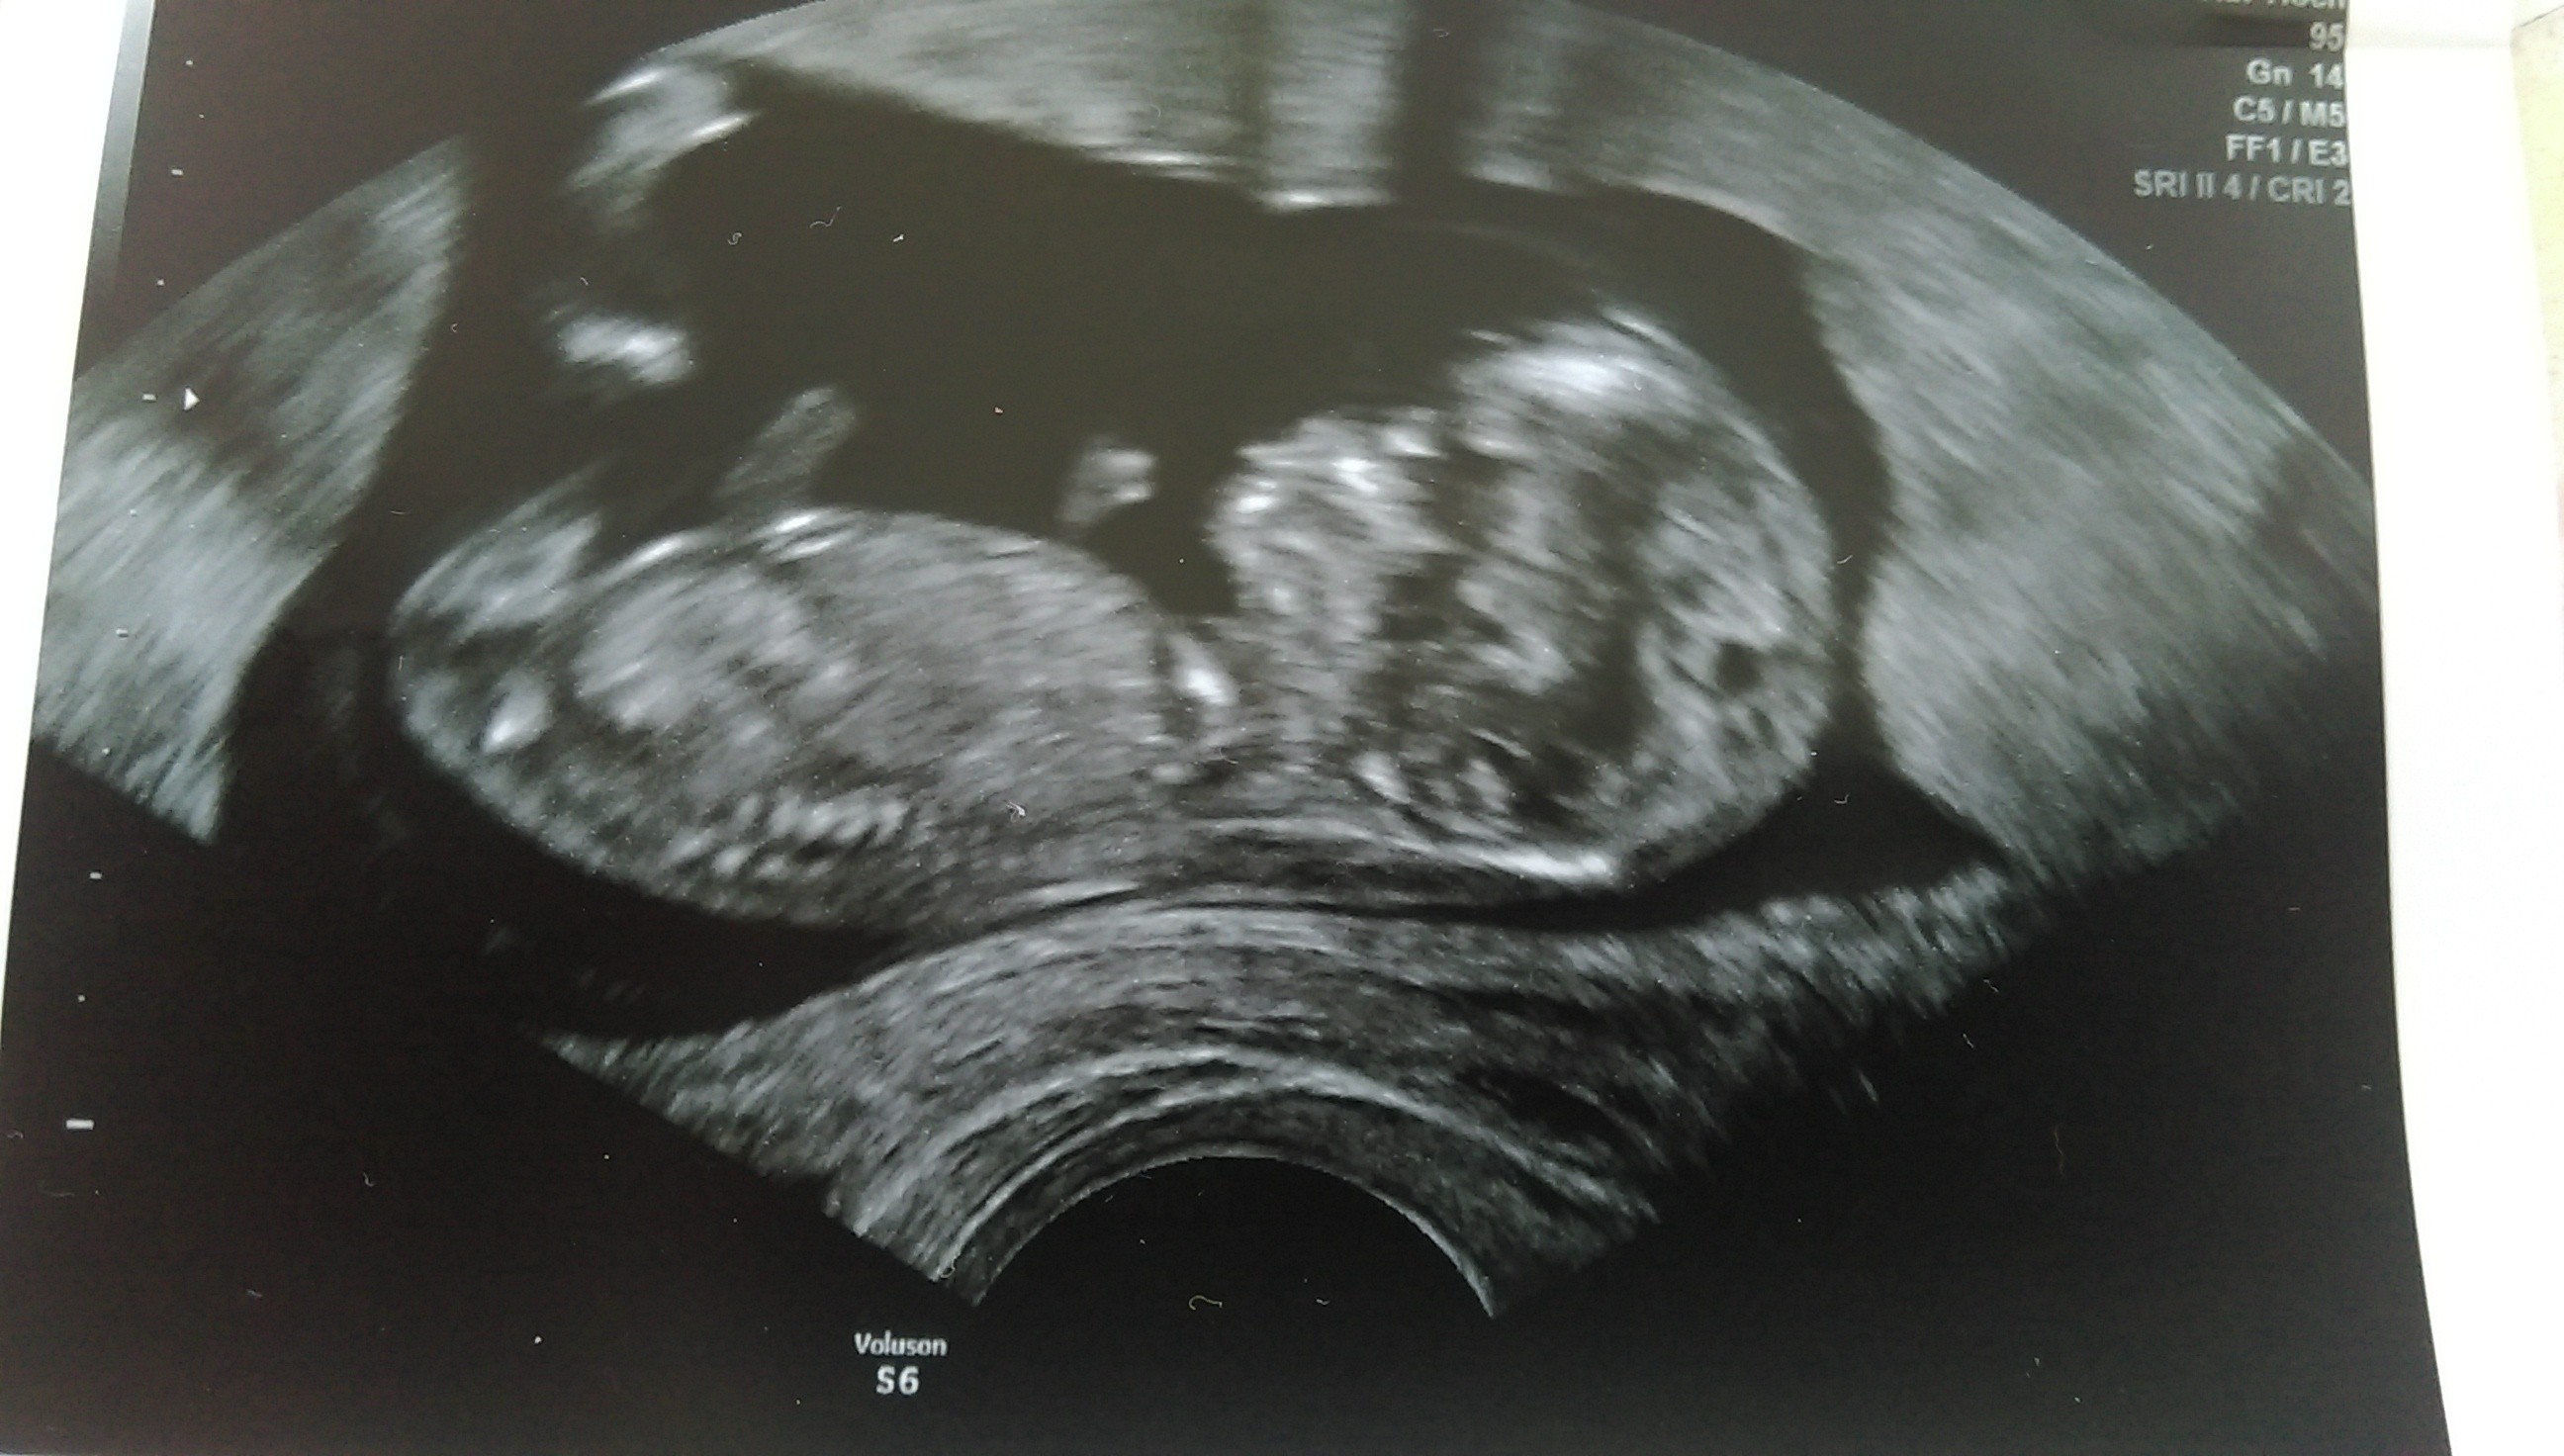

Hej dziewczyny. Ja już po wizycie, maluchy świetnie się mają, ładnie rosną, według OM to 10t4d według USG 11t4d.

Dostałam również skierowanie na badanie prenatalne z testem PAPPA na NFZ.

Ogółem po krwiakach ani śladu, wszystko dobrze jedynie dostałam jeszcze urosept bo mam liczne bakterie w moczu, CRP lekko podwyższone i w morfologi leukocyty też powyżej normy... Ale ogółem wszystko OK.

8.06 mam badania prenatalne + test PAPPA a 16.06 zwykła wizytę kontrolną...

Oto przedstawiam Wam moje WSPANIAŁE DWIE KRUSZYNKI ❤❤